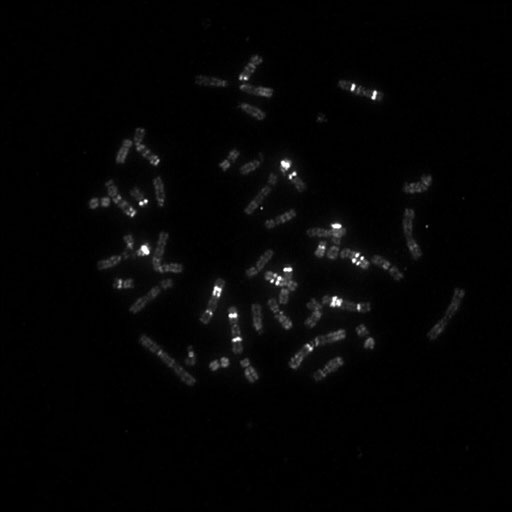

081 M